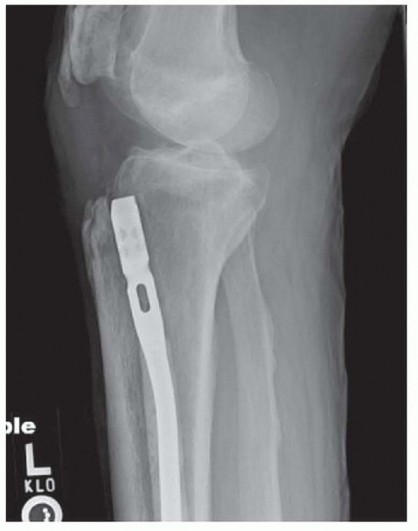

- C. A specialized, long insertion handle is required for suprapatellar techniques to reach the tibial start site. Locking bolts found in the nailing set or screws made from the same metal as the nail should be used. Blocking screws can either be placed prior to initial nail insertion or, if the nail is inserted and residual deformity exists, the nail can be removed and blocking screws can be inserted. Coronal and sagittal plane correction can be performed by placing a screw at the concavity of the deformity. To correct valgus, the screw is placed laterally ( TECH FIG 13A). To correct lateral plane extension, the screw is placed posteriorly (TECH FIG 13B). The appropriately sized drill bit is placed with fluoroscopic assistance. The appropriately sized screw replaces the drill bit. The guidewire is then inserted and seated distally. Intramedullary reaming is necessary to ensure the nail follows the newly created path. When a screw that blocks the way is encountered, simply push the reamer head past the screw without reaming. This avoids dulling the reamer head and potentially displacing the blocking screw. Once passed the screw, resume reaming. After reaming is complete, insert the intramedullary nail. If the displacement has not been corrected, it will be necessary to remove the nail, and additional screws may be added. Reaming and reinsertion of the guidewire are required before reinserting the nail. Interlocking bolts through the nail are placed in the standard fashion ( TECH FIG 13B,C). 561 ### TECH FIG 13 • A. A blocking screw positioned just lateral to the ideal nail path to prevent valgus deformation.

| ### B. A posterior blocking screw limits proximal fragment extension by limiting the effective anterior to posterior canal diameter. B,C. Lateral and AP fluoroscopic imaging showing oblique and medial to lateral interlocking bolts placed through the nail.